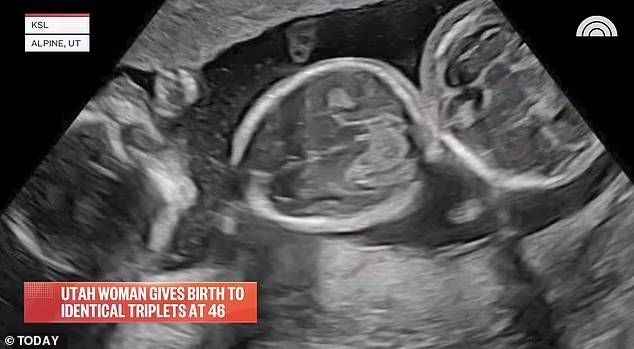

TEK YUMURTA ÜÇÜZÜ DOĞURDU!

Çift, 30 Mart'ta, üçüz oğulları Sky, River ve Bay'i karşıladılar. Böylece Audrey’nin yeniden anne olma hayali 46 yaşında gerçek oldu.

Bu aynı zamanda tıbbi anlamda bir mucizeydi çünkü istatistiksel olarak 45 yaşında bir kadının doğal yollarla tek yumurta üçüzlerine sahip olabilme ihtimali 20 milyarda bir.